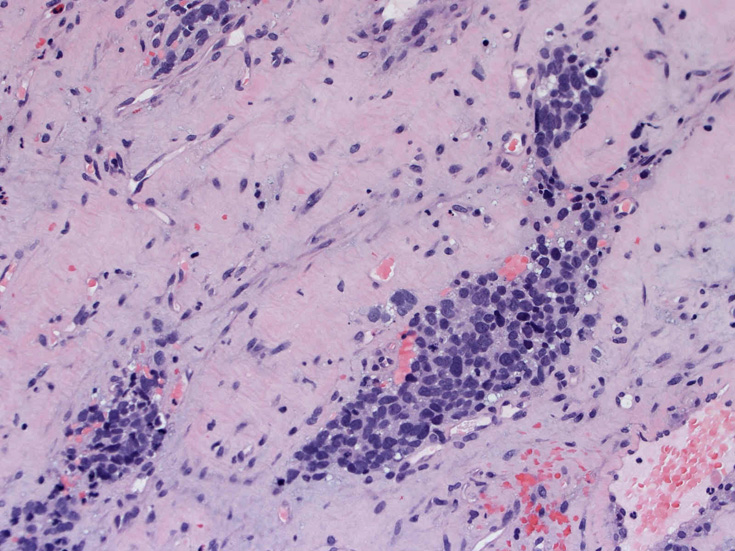

症例--鼻腔腫瘤

30歳代男性 鼻腔腫瘤の生検組織

厳密にはalveolar patternが明らかではなく, solid typeに入る症例かもしれない。異型細胞増殖胞巣が線維化組織に取り囲まれるように散在している. 小さな生検組織のため全体像が不明である。

鼻腔腫瘤生検組織